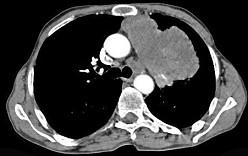

问题 56岁,男,意识错乱情绪不稳定一周,请结合胸片和CT,选出最可能的诊断 ( )

选项 A、韦格肉芽肿 B、胸腺瘤 C、错构瘤 D、胸内甲状腺肿 E、肺癌

答案 E